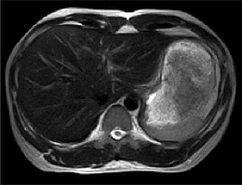

MRIは磁気共鳴画像とも呼ばれ、強い磁石と電波を使って、身体のあらゆる部位を撮影できる装置です。放射線を使用しないので被ばくの心配はなく、ラジオ波と同じ電波を利用して撮影しているため人体に優しい検査法です。 X線の画像と比べて筋肉・脊髄・内臓などが、明瞭かつ詳細に描出されます。MRIが有用なのは、脳梗塞・脳腫瘍などの脳疾患、動脈瘤などの血管障害、がん・子宮筋腫・椎間板ヘルニア・靭帯断裂など動きの小さい柔らかい組織での病変描出に適しています。 MRIの特性を利用して、造影剤を使わずに脳血管像(MRA) 胆管・膵管像(MRCP)の描出も可能です 。

実際の検査画像

| 頭部 | 頸椎 | 腰椎 | 腹部 |